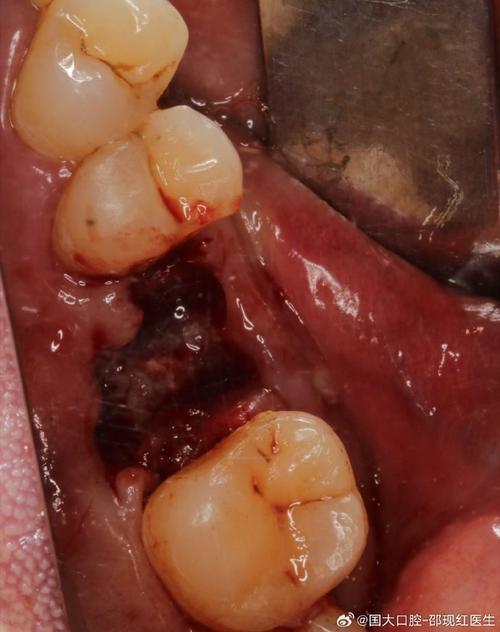

感染(细菌性炎症)

(图片来源网络,侵删)- 表现:持续肿胀加剧、疼痛明显、牙龈流脓、口臭、发热。

- 原因:

- 术中/术后细菌污染(如器械消毒不彻底、口腔卫生差)。

- 创口裂开、异物残留(如骨碎片)。

- 免疫力低下或未遵医嘱服用抗生素。